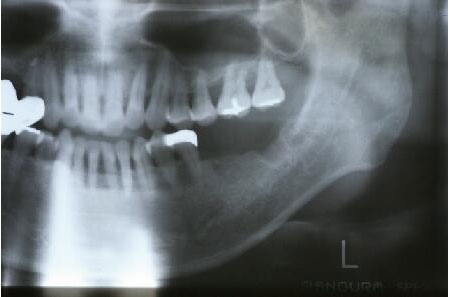

抜歯後エックス線写真

3ヵ月後の抜歯部